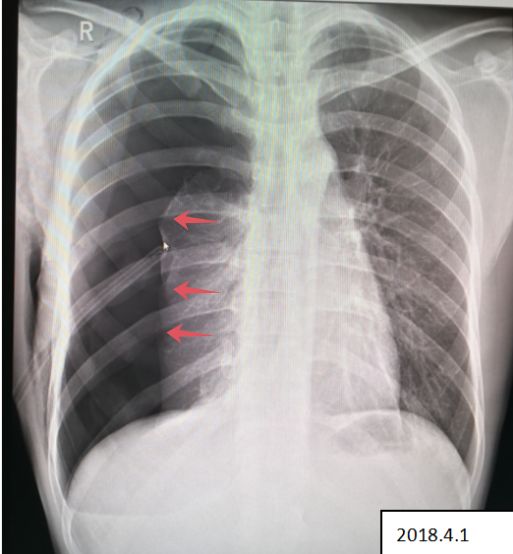

杨某,男,25岁,参加篮球比赛突发胸痛、呼吸困难,送医院检查。

病例6患者的X线胸片

患者右侧肺野内见带状异常透亮无肺纹理区,内侧缘可见发线状被压缩肺组织外缘(红色箭头),被压缩约75%以上,两肺门影不大,肋膈角清晰、锐利,心影形态、大小正常,纵隔稍向左移位。

2018.4.1 患者复查X线图像

患者右肺气胸复查所见:右侧肺野外带(约占肺野4/5)见带状异常透亮无肺纹理区,内侧缘可见发线状被压缩肺组织外缘,被压缩约75%以上,内可见引流管置入影。 右侧胸壁可见气体影。